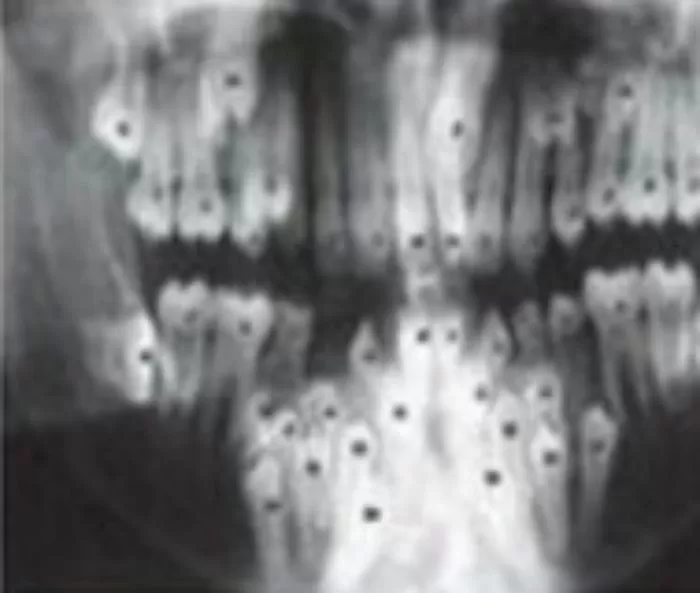

지난 5일(현지 시간) 온라인 미디어 'eva'는 치아 과다증이라는 희귀질환으로 유치만 300개가 난 소년의 엑스레이 사진을 공개했다.

필리핀 세부에서 태어난 소년 존크리스 칼 퀴란테(Johncris Carl Quirante)는 입 속에서 약 300개의 유치가 발견돼 의료진을 경악게 했다.

처음 존크리스의 치아 상태를 엑스레이로 확인한 의료진은 처음 보는 광경에 말문이 막혀 한동안 말을 잇지 못했다.

이미 입에는 더 이상 치아가 들어설 곳이 없었고 이대로면 외적으로도 심각한 후유증이 생길 수 있는 상황이었다.